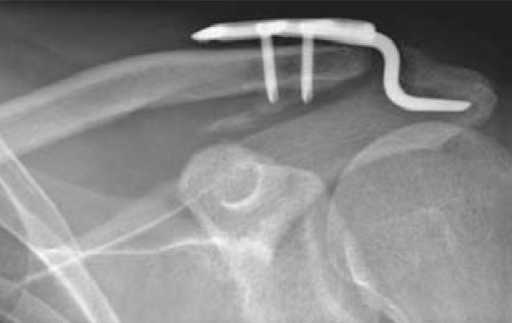

Недавно наткнулся на такого рода "новшество" - пластинка от АО для фиксации разрывов акромеально-ключичных сочленений.

фото приложил.